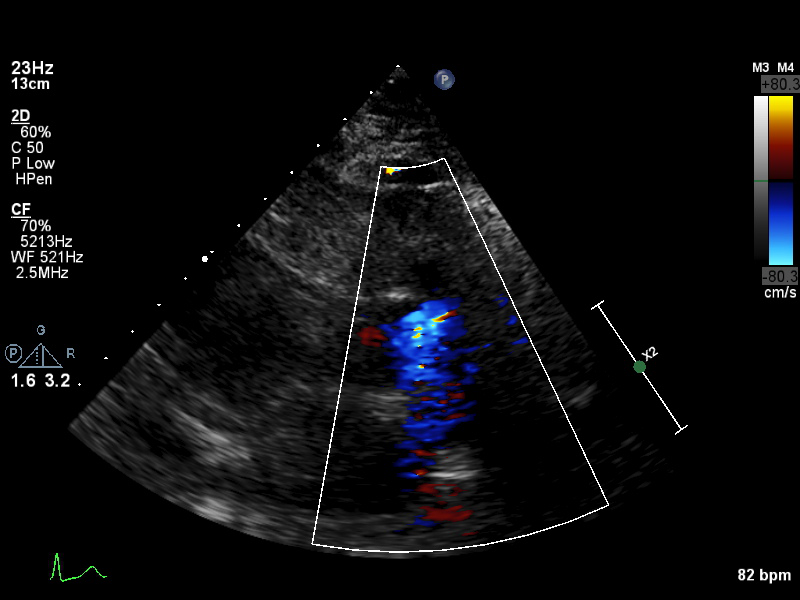

a4ch-ra a4ch-ra Apical 4-chamber focused on the right atrium, or colour Doppler on TV/RA

a4ch-rv a4ch-rv Apical 4-chamber focused on the right ventricle